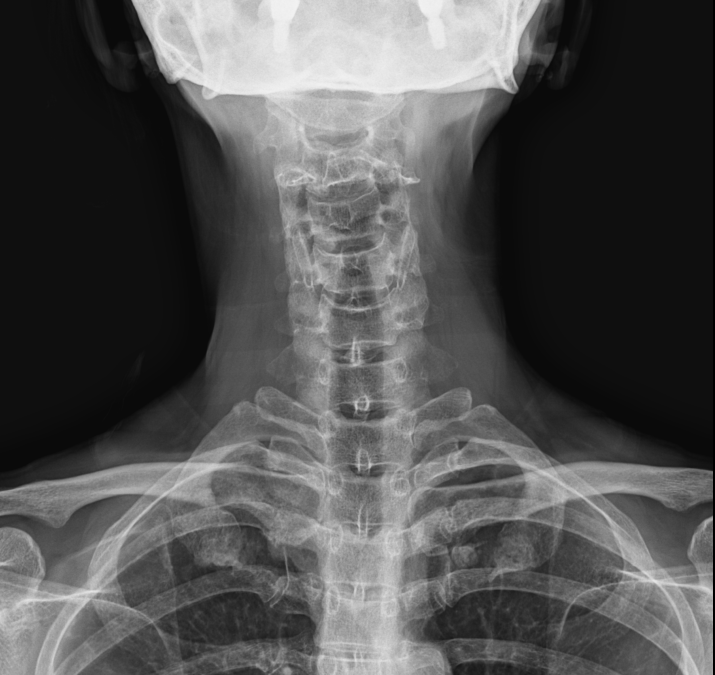

로벳반응계(Lovett Reactor)에서 경추 1,2번 목뼈가 우측으로 틀어지면 요추 4,5번도 우측으로 틀어지고 경추가 좌측으로 틀어지면 요추도 좌측으로 틀어진다는 규칙을 연구하였습니다.

사경증도 경추가 휘어져서 생긴 후유증, 경추1,2번부터 교정을 해야한다. 그렇기 때문에 치아의 교합이 엉망이면 목이 틀어지게 되고 허리도 같이 틀어진다는 결론을 생각할 수 있습니다. 경추 1,2번은 항상 빠져있는데 그렇다면 경추와 요추가 항상 틀어지게 된다는 것을 또한 알 수 있습니다. X-ray, MRI 같은 2차원적인 검사 외에 척추와 골반의 특수 촬영을 한 영상을 보면 뇌척수액의 흐름에 따라 골반도 같이 움직이는 것을 볼 수 있었고 뇌척수액의 흐름이 원활하려면 척추가 바른 자세에 따라 뇌척수액이 잘 흐른다는 것도 확인되었습니다. 가부좌, 도인법과 같은 선법이나 양생법도 결국에는 척추를 바르게 해 주고 뇌척수액의 흐름이 좋게 열어주는 재활치료라고 할 수 있습니다.https://naver.me/FgiE6Sux

사경증이나 목디스크, 허리디스크 환자들을 그 아픈 부위만 물리치료와 시술, 도수치료를 하지만 허리 환자들이 40년, 50년을 허리치료를 받는 것으로 미루어 본다면 좁아진 목, 허리디스크 간격은 그대로 있고 통증만 앉히는 치료를 맴돌고 있는 실정입니다. 좁아졌거나 휘어진 척추들이 원래의 바른 척추모양으로 돌아가면 디스크가 닳아 없어졌어도 좁아진 상태에서 약물치료만 받는 것보다는 훨씬 통증이 부드러운 근본 치료가 될 것이라고 생각됩니다. 24마디 척추뼈 중에 1 마디뼈가 빠져있으면 전체 척추뼈들은 왁구가 잘 맞지 않은 부속이 안 맞아서 버려진 장난감 같은 척추 상태라고 할 수 있습니다. 고통받으시는 환자분들께는 매우 죄송한 표현입니다만 경추 1,2번 뼈가 빠져있다는 것을 가장 이해하기 쉬운 설명일 것입니다. X-ray 1장 찍고 이상 없다고 하는 것보다는 해부학적인 설명이죠.. 턱관절은 우리 몸의 모든 관절을 통제하는 마스터 관절(Master joint)입니다. 목뼈가 빠져서 척추가 틀어지기 시작해서 목뼈를 일자로 변형을 시키고 허리까지 변형을 주는데 요추 4,5번이 특히나 잘 좁아지는 부위인 것입니다. 흉추 15번 디스크는 제가 임상 20년 중에 아직은 못 봤습니다. S곡선이 있던 요추가 잘 튀어나가거나(전방전위증), 디스크가 좁아지고 붙어버리는 것이 오기가 쉬운 것입니다. 좁아진 요추를 벌리는 치료가 수술만 있는 것이 아닙니다. 경추 1,2번이 빠져있는지 확인을 하고 틀어져 있다면 경추 1,2번을 정렬(Alignment) 시켜주면 너무나 고맙게도 3번부터 24번까지 척추는 경추 1,2번과 인대, 근육을 따라서 차례차례 다시 줄을 서게 됩니다. 골반교정을 하고 Drop을 치고 근육을 풀고 할 일이 아니라 척추뼈를 움직이는 치료를 받아야 합니다. 그런데 이 경추 1,2번을 가장 많이 비틀고 누르는 것은 부정교합, 턱관절이라는 것이 중요합니다.